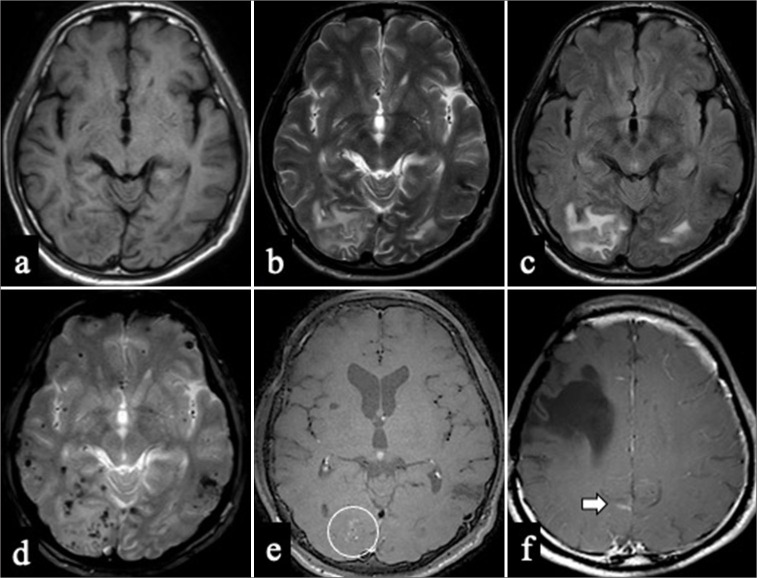

Case description: A 50-year-old man with a history of childhood right frontal hemorrhage and epilepsy presented with right upper-limb numbness. Computed tomography revealed a left parietal subcortical hemorrhage, and MRI showed bilateral occipital white matter hyperintensities, microbleeds, and right occipital leptomeningeal enhancement. Biopsy of the right occipital lesion confirmed amyloid-β deposition with mild perivascular lymphocytic infiltration, indicating probable CAA-ri. He was managed conservatively owing to the minimal mass effect and received corticosteroids as outpatients. MRI at 19 months revealed resolution of occipital hyperintensities, without neurological deficits.